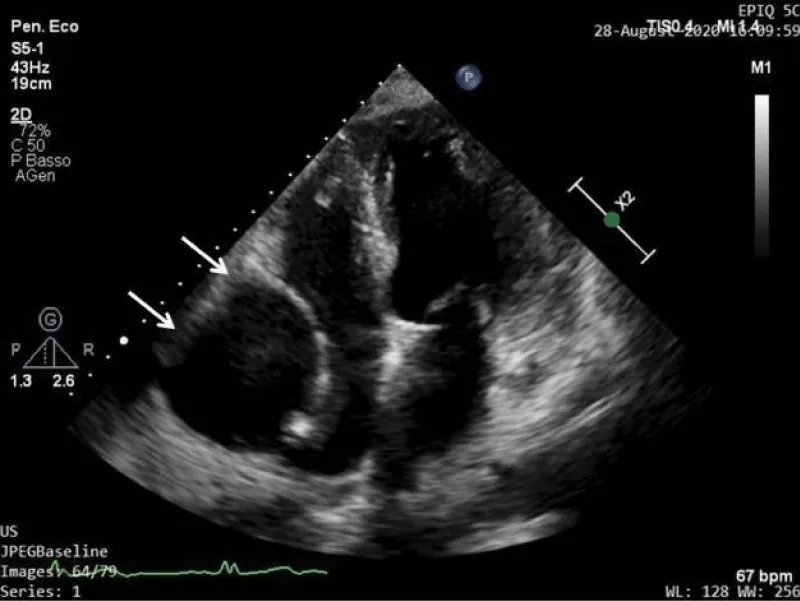

We performed echocardiography that showed normal size and function of the left ventricle and confirmed the presence of a giant round cystic-appearance lesion at the level of the right atrioventricular groove with mild compressive effect on the right chambers. The lesion was characterized by the presence of an anechoic space with an internal echogenic swirling flow pattern (Figure 2). The color Doppler mode showed a faint signal, without clear evidence of flow origin and it was not possible to sample any conclusive PW-Doppler signal.

Figure 2: 2D echocardiography (4 chamber view) shows the presence of a giant round cystic-appearance lesion characterized by the presence of an anechoic space with an internal echogenic swirling flow pattern.

We firstly excluded a pericardial cyst because of the echo appearance of the lesion with anechoic space and internal echogenic swirling flow pattern, highly suspicious for blood flow. To better characterize the flow, color-Doppler and PW-Doppler were performed with inconclusive results. The bubble test also excluded communication between the lesion and right cardiac chambers or systemic veins.

After administration of a single bolus (2 ml) of SonoVue® and right chambers opacification, the lesion did not show any contrast uptake. After complete opacification of the left side chambers and the aorta, we noticed a very limited flow origin localized at the atrioventricular junction. The flow was directed towards the wall of the lesion displaying a swirling pattern.

Finally, the contrast injection allowed us to better visualize the color-Doppler signal confirming the high velocity flow at the origin and circular pattern inside the lesion. It was also possible to sample PW-Doppler which confirmed an ECG-syncronized system-diastolic flow typical for coronary artery flow.